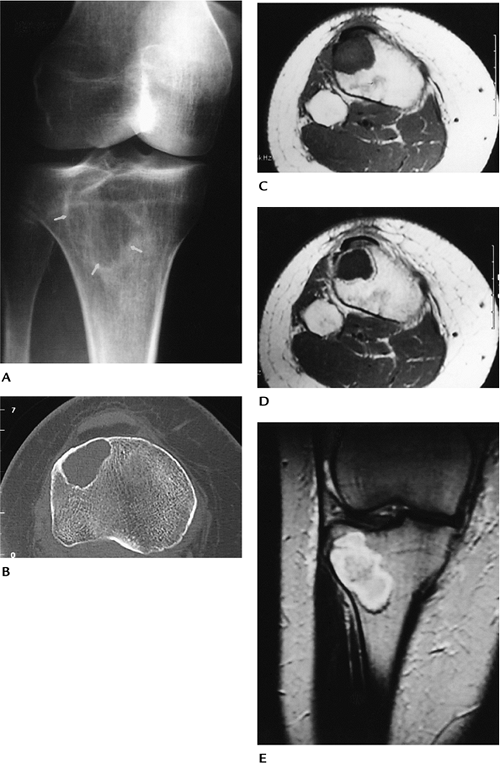

FIGURE 10-16 Chondromyxoid fibroma in a 45-year-old woman. (A) Oblique radiograph of the knee showing a lytic lesion with sclerotic margins (arrows). (B) Axial CT showing the well-defined sclerotic margins with no matrix calcifications. Axial T1-weighted (C), axial enhanced T1-weighted (D), and T2-weighted coronal (E) images showing the lesion to be low signal intensity on T1 (D) with peripheral enhancement.